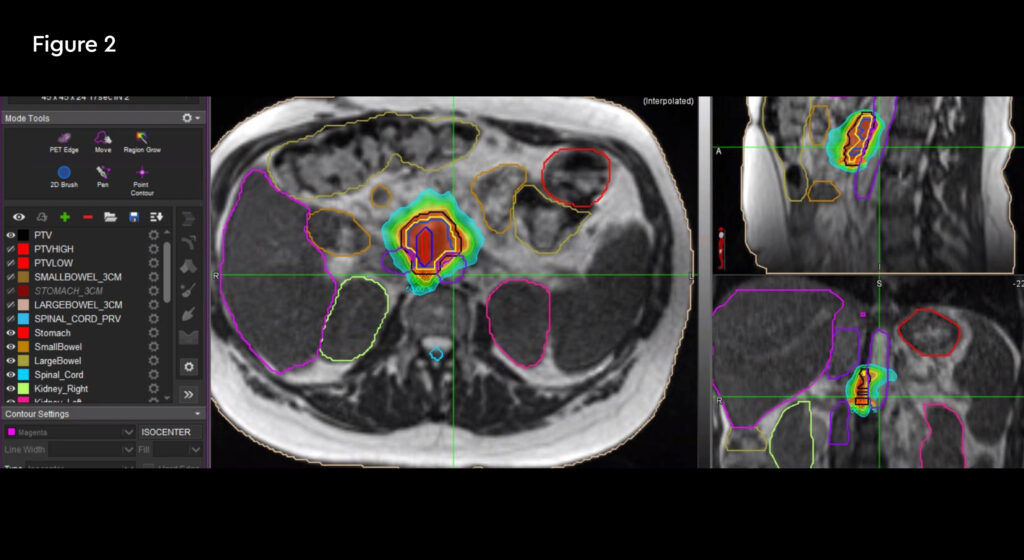

Figure 1: MR and PSMA PET fusion showing recurrence

A 52-year-old female with metastatic renal carcinoma. At the time of referral for stereotactic ablative radiotherapy (SABR) she had oligoprogressive disease in a single lymph node beneath the right diaphragmatic crus (figure 1).

The patient was initially diagnosed in October 2018 when she also underwent an open right radical nephrectomy confirming the presence of renal clear cell carcinoma with rhabdoid change, stage T3bNxMx. Further investigation revealed the presence of multiple pulmonary metastases and she was commenced on nivolumab and ipilimumab immunotherapy treatment. Her metastatic disease had been completely controlled with no evidence of growth until a routine check CT scan identified an enlarging right upper abdominal node adjacent to the right diaphragmatic crus. At the same time, she developed right upper abdominal pain which was thought to possibly be due to the nodal growth but also possibly due to gallstones which she was also known to have.

Fig 1: Pre-treatment CT scan showing right upper abdominal node measuring 25mm on 10th January 2020